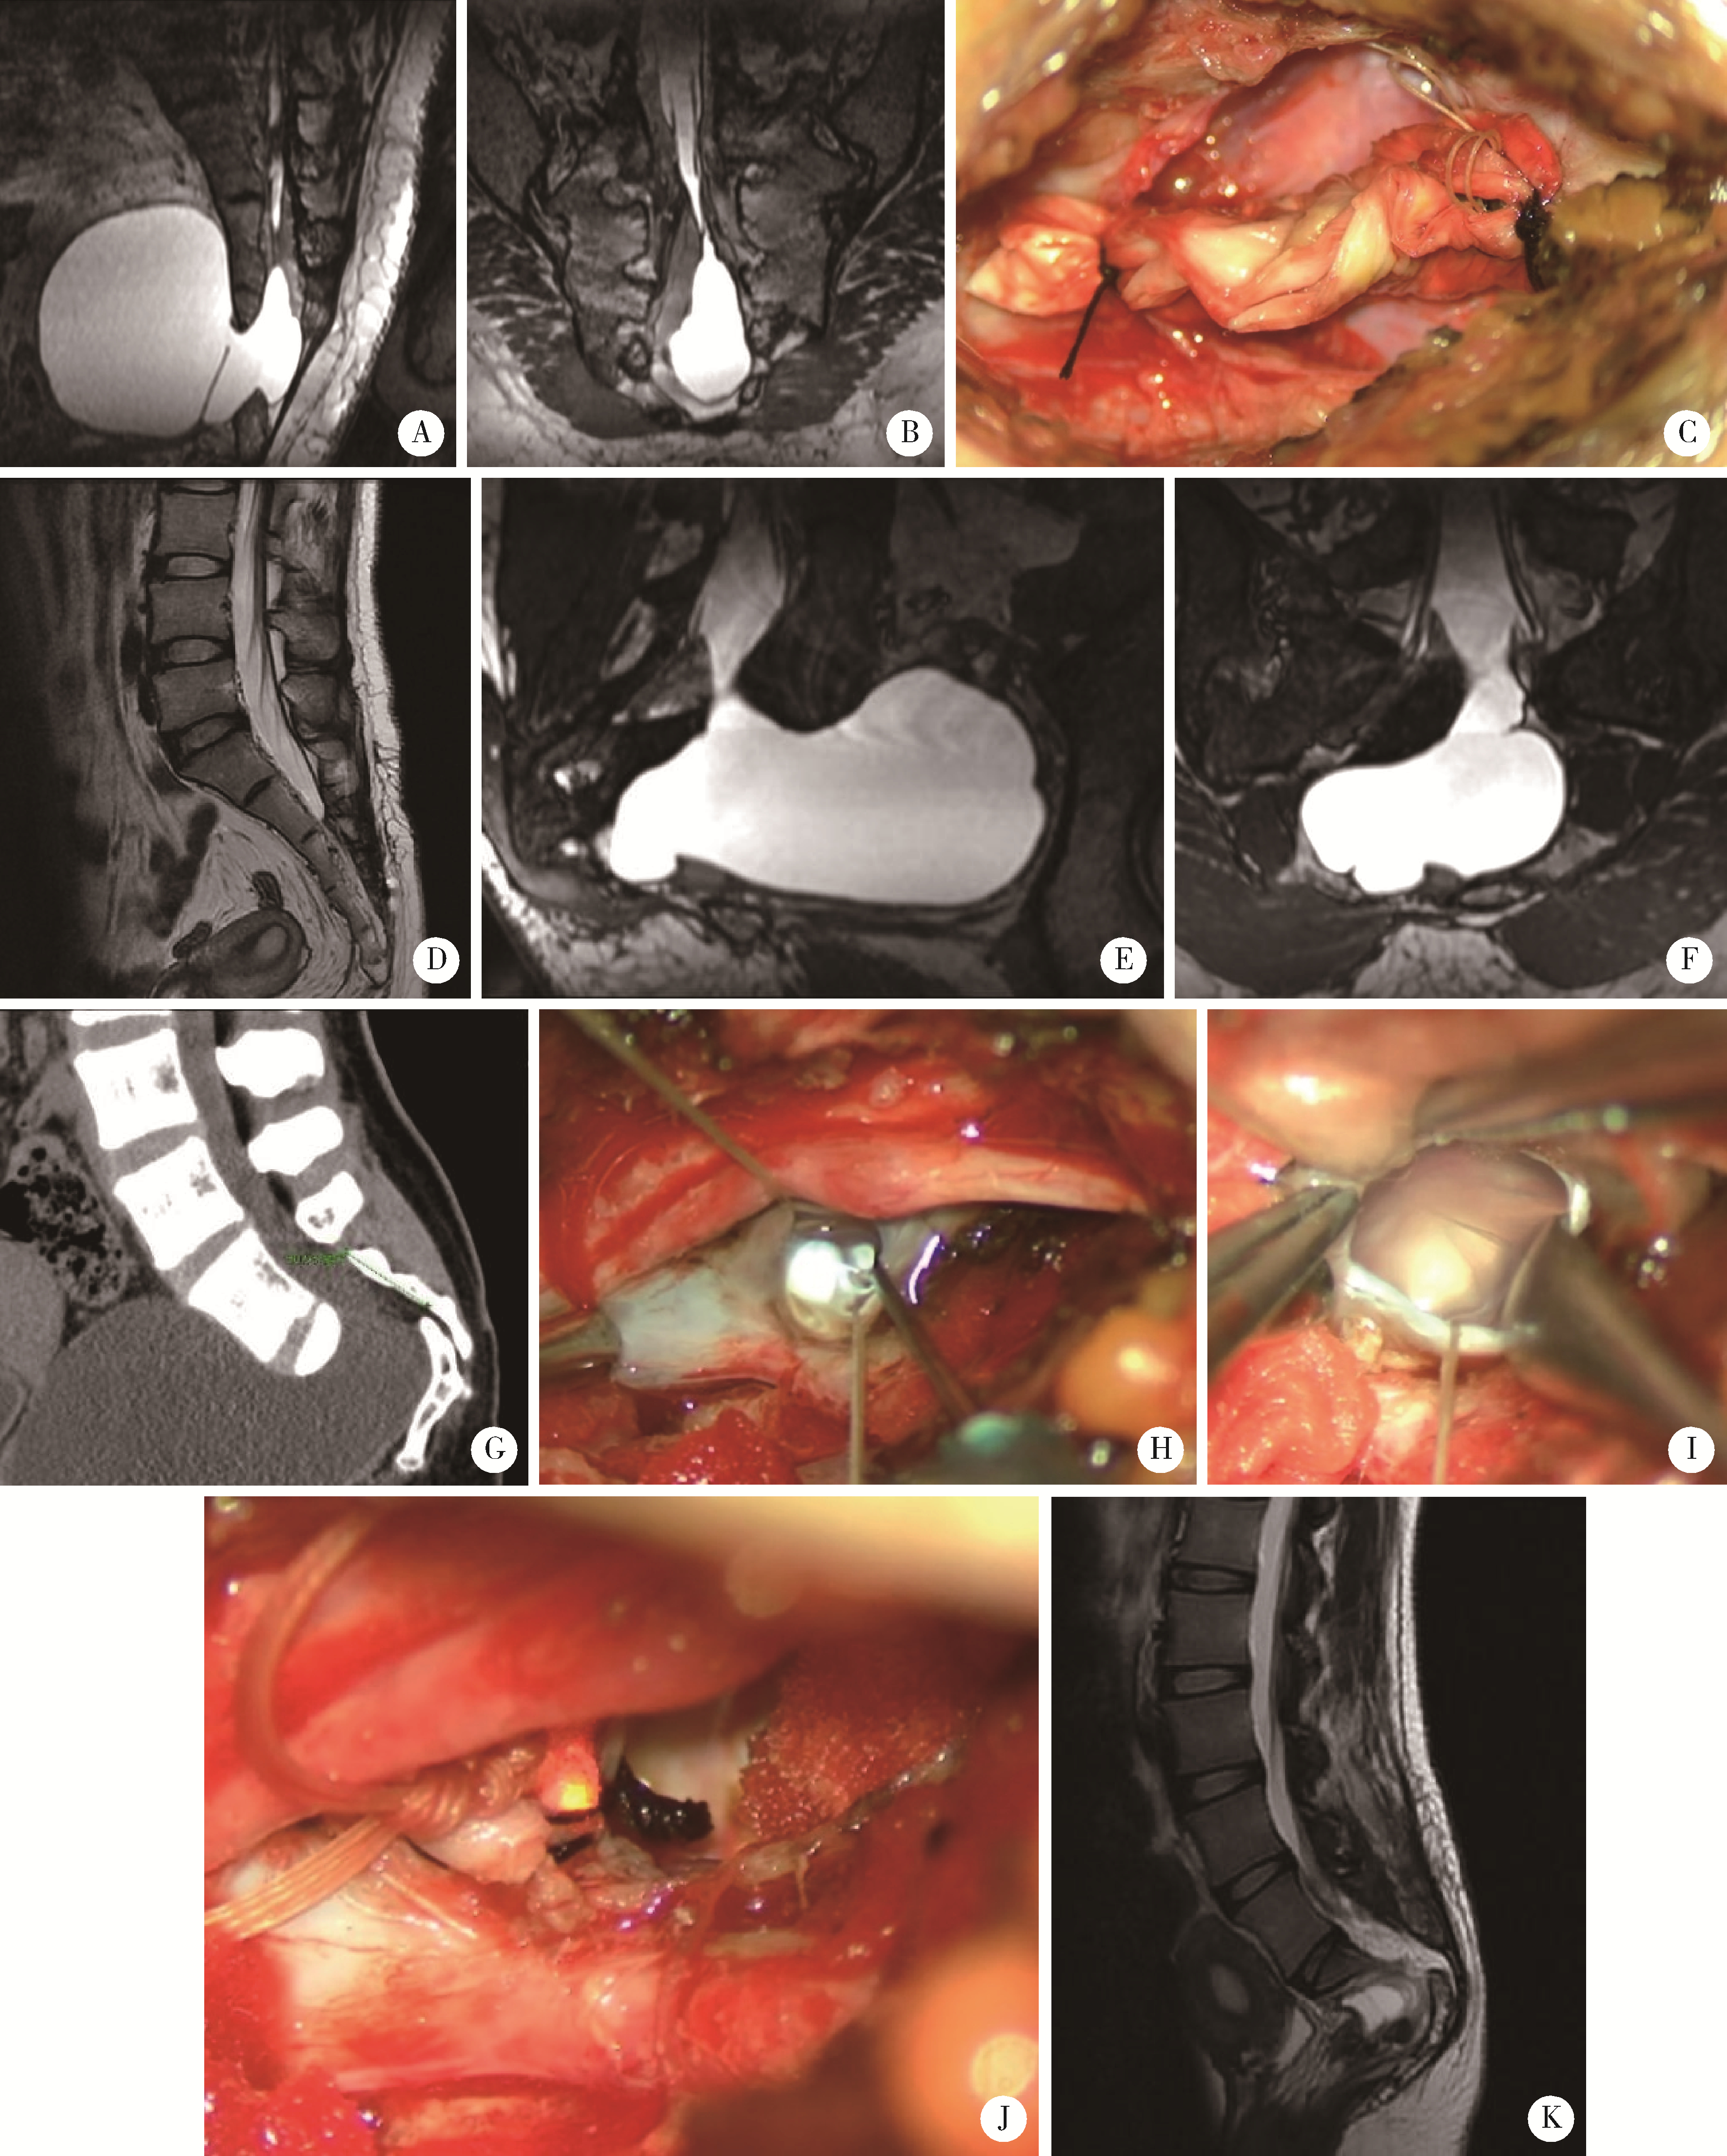

图1

内含神经根囊肿的不同类型"

图2

内无神经根型骶管囊肿的各种类型"